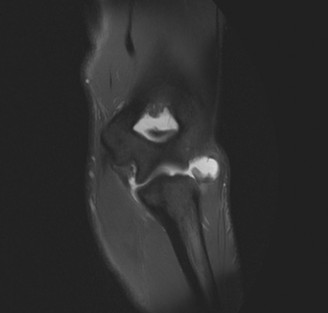

Treat a patient with scapular winging? CASE 23 A 47-year-old, right-hand-dominant male presents to your clinic complaining of right shoulder weakness for the past 2 months. He denies any history of trauma but notes sudden onset of pain 2 months ago that lasted approximately 2 weeks and then subsided without any intervention and was followed by shoulder weakness. He works as a lawyer and has been going through a divorce for the past year. Physical examination reveals no tenderness to palpation about the shoulder. He has decreased sensation over the lateral aspect of the shoulder, decreased muscle bulk over the left shoulder compared with the contralateral side, and weakness with left shoulder abduction. He is distally neurovascularly intact. The patient had already been referred for an x-ray and MRI by his primary care doctor that are shown in Figures 2–62 and 2–63.

Figure 2–62

Figure 2–63

Injury to what structure is most likely responsible for his symptoms?

- Axillary nerve

The correct answer is (C). The patient’s decreased sensation over the deltoid, deltoid muscle atrophy on examination, and MRI with atrophy of the teres minor points to axillary nerve dysfunction. Suprascapular nerve injury (Choice A) would result in atrophy of the infraspinatus and or infraspinatus muscles, leading to weakness with external rotation and/or forward flexion. Dorsal scapular nerve injury (Choice B) would result in weakness of the rhomboid muscles and levator scapulae. While injury to the posterior cord of the brachial plexus (Choice D) would result in symptoms of axillary nerve palsy, they would also involve dysfunction of the radial nerve, which also comes off the posterior cord.